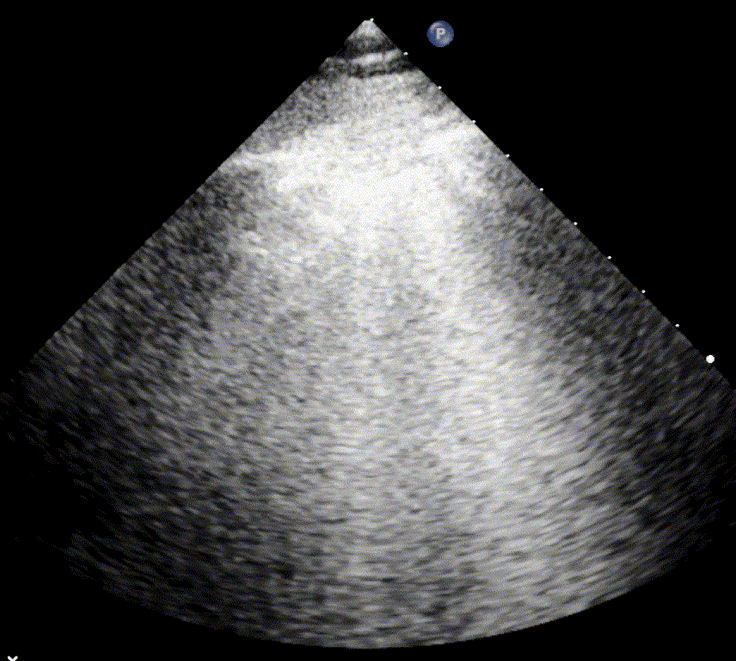

Pleural effusion

Pleural effusion refers to the accumulation of fluid between the parietal and visceral pleural layers. Because pleural fluid gravitates to the most dependent areas, it is typically detected in the lowest portions of the thoracic cavity. Diagnostic sensitivity increases when the patient is in a sitting position, as gravity allows the fluid to collect inferiorly. The lung tissue adjacent to the effusion is often compressed and partially air-depleted.

Scanning the posterolateral chest zones is most effective for identifying pleural effusions. Effusions are commonly found at the lung bases and in the costophrenic angles, where the diaphragm meets the chest wall. Compared with chest radiography, lung ultrasound is both more sensitive and more specific for detecting small volumes of pleural fluid.

Ultrasound can also be used to estimate the volume of pleural effusion. The simplest method is described by Balik et al., which involves measuring the maximal vertical separation (in millimeters) between the diaphragm and the lung base in a supine patient, and multiplying this value by 20 to approximate the pleural fluid volume: Pleural Volume (mL) = Maximal distance (mm) × 20. This formula provides a practical estimation of pleural fluid volume in clinical settings.

Loculated/Septated Pleural Effusion

Loculated pleural effusions, also referred to as septated effusions, are typically associated with exudative pleural processes. The term describes effusions in which the pleural fluid is divided into multiple compartments or “pockets” by fibrous septa.

These loculations arise from inflammatory or infectious processes, such as empyema, abscess formation, scarring, or fibrosis in the pleural cavity, which interfere with normal fluid movement and drainage within the pleural cavity.